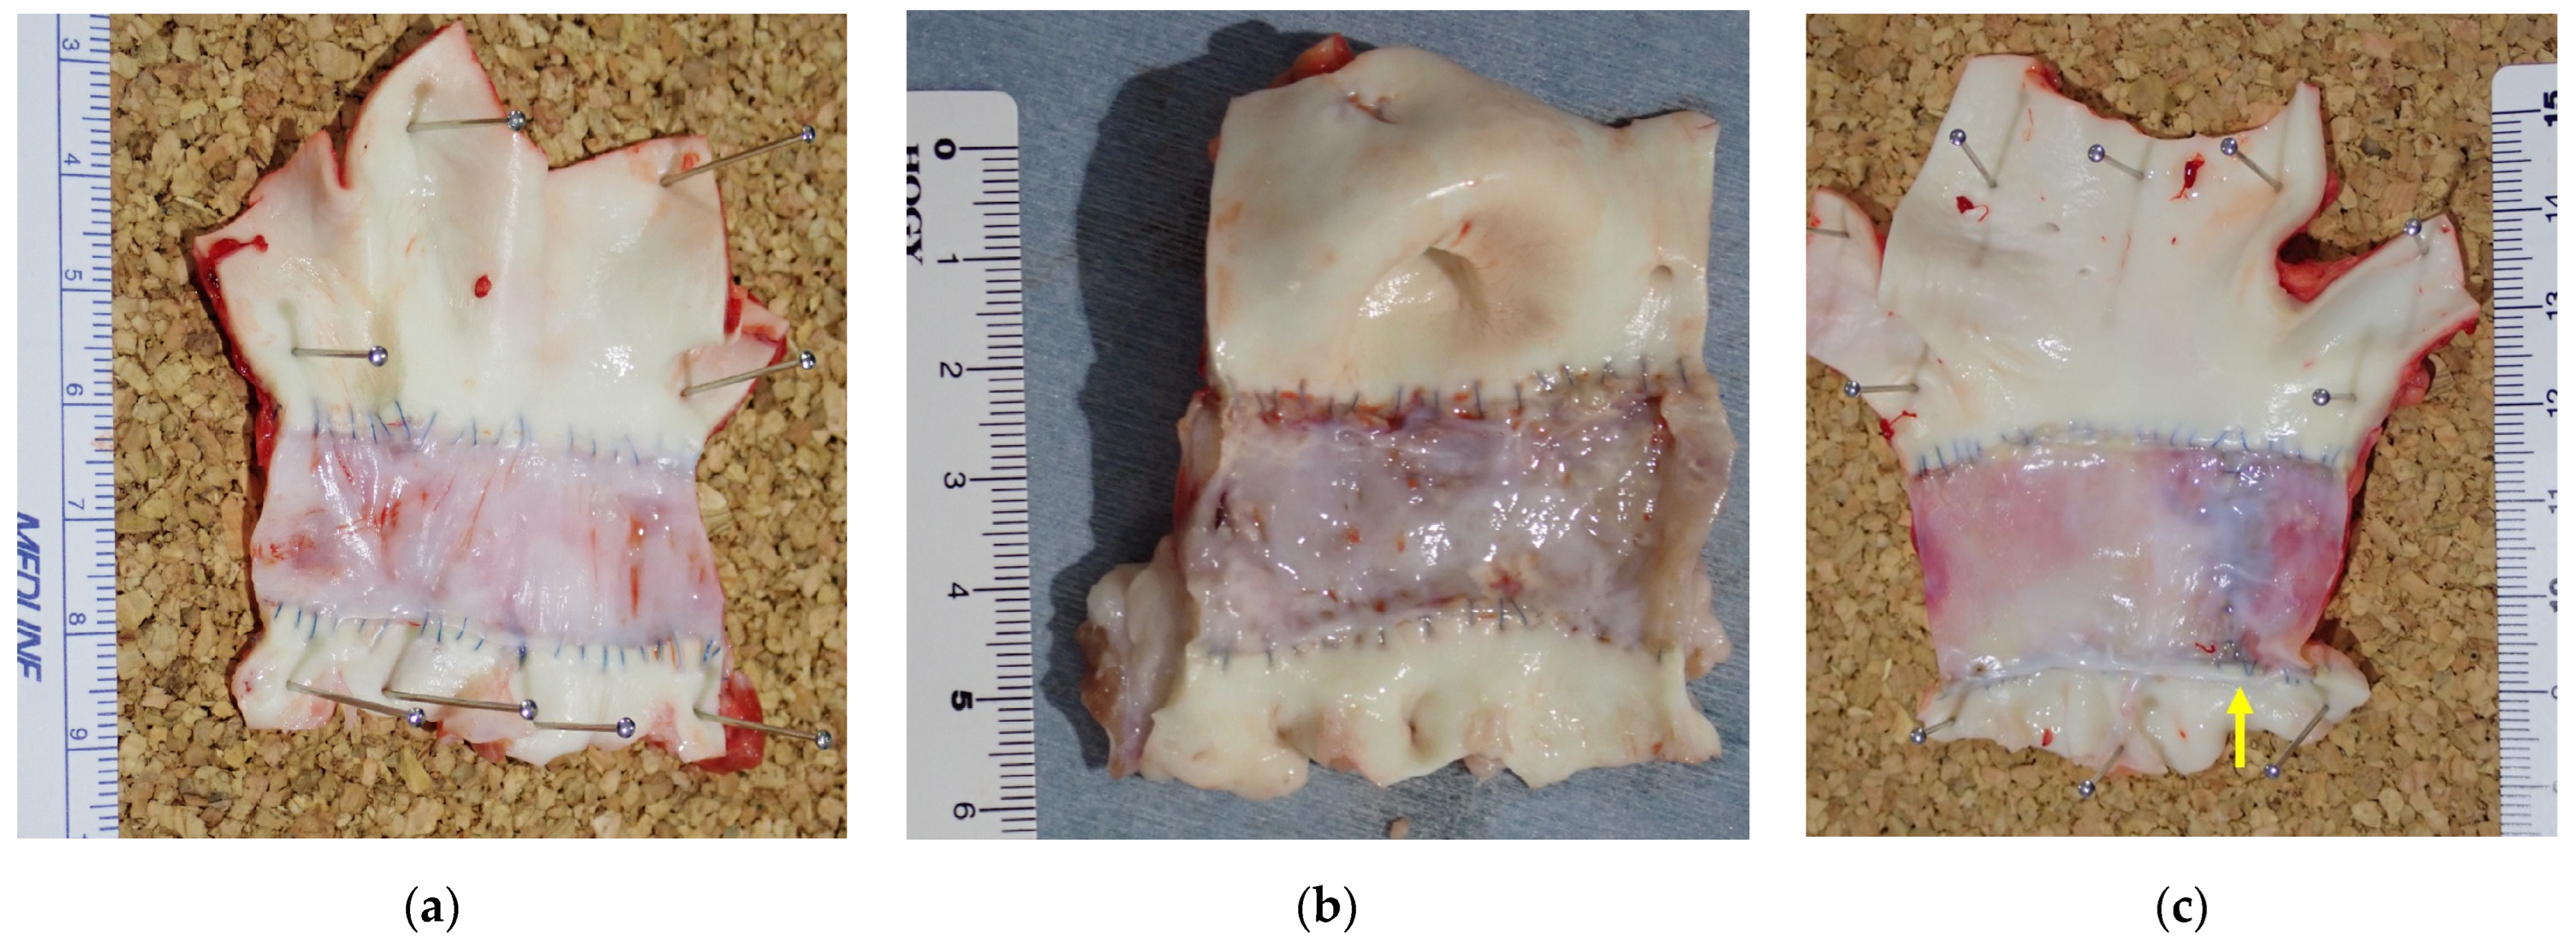

3.3. Histologic Evaluation